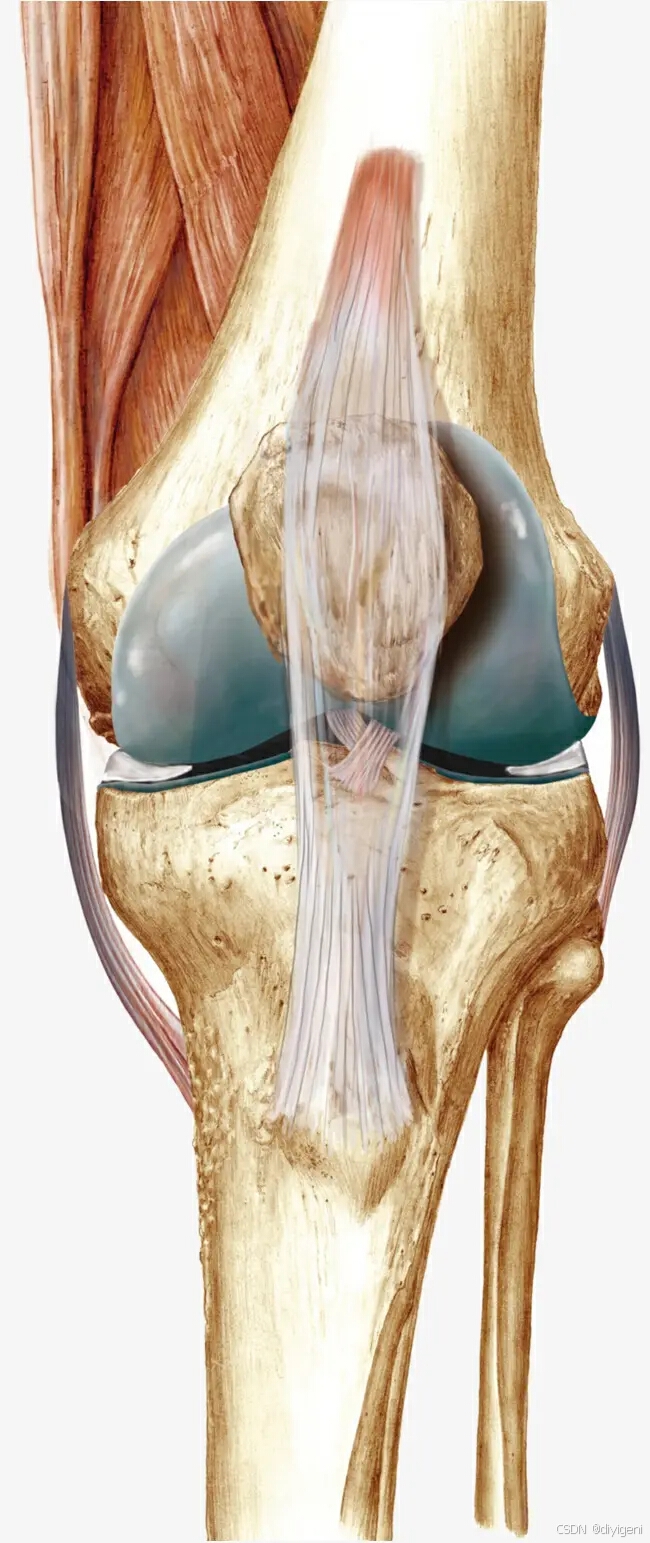

髌骨软化症是髌骨的软骨损伤引起的退行性变化,包括软骨的肿胀、碎裂、脱落和腐蚀等病变,而产生的一系列症状。最后股骨与髌骨相对应的关节面也发生同样的变化,并逐渐形成髌股关节的反应性增生,后期将形成骨关节炎。